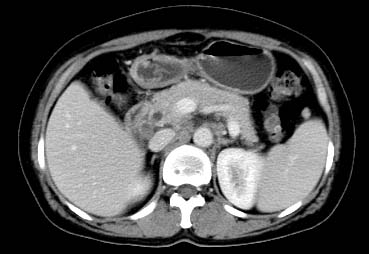

以下是引用西北一只狼在2008-6-30 20:58:00的发言:[br]肝左叶胆管细胞ca并肝门淋巴结转移、胰腺、胃小弯浸润

以下是引用ydx_74在2008-6-30 21:54:00的发言:[br]左叶胆管细胞ca并肝门淋巴结转移、胰腺、胃小弯浸润